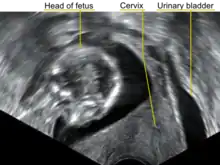

| A transvaginal ultrasound showing a retroverted uterus during pregnancy. The cervix lies posteriorly to the urinary bladder, and the uterus normally extends superiorly from it, but the direction of the body of the fetus reveals that the uterus extends backwards. | |